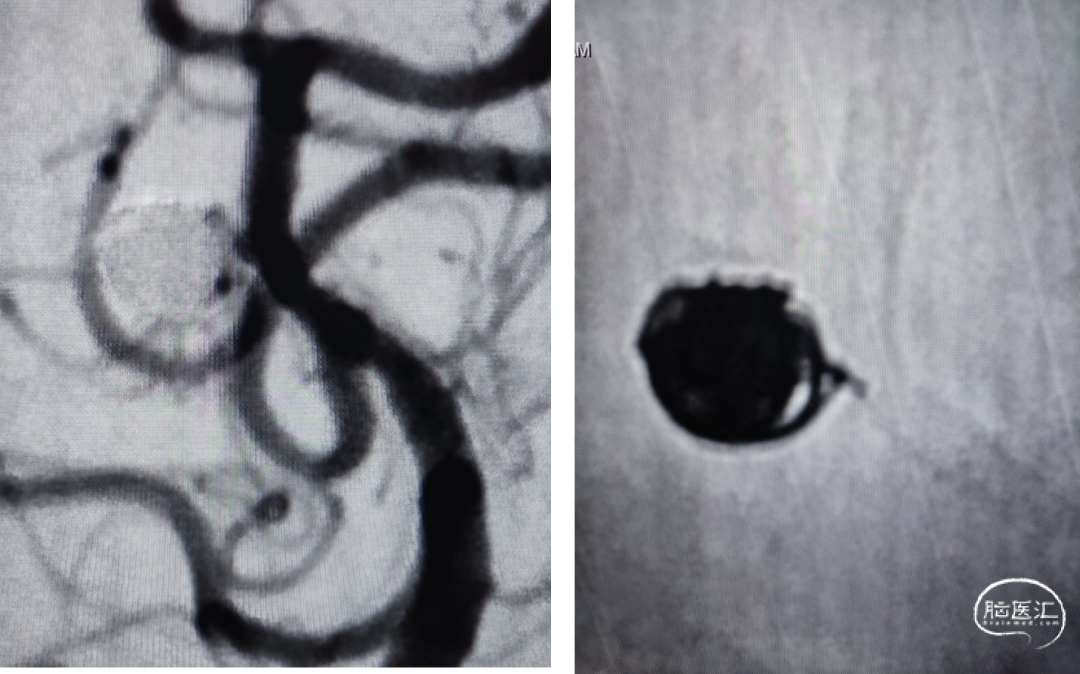

一般项目:患者女 年龄:71岁;

因“检查发现脑内动脉瘤10天”入院;

外院造影检查发现右侧大脑中动脉M1段动脉瘤、右侧颈内动脉眼动脉段动脉瘤。

既往史:既往有高血压、糖尿病病史。

⇨FD结合弹簧圈动脉瘤栓塞术

Lattice 2.6x18

泰杰 6mm*20cm 3D、 泰杰4.5mm*12cm 3D、 泰杰3mm*6cm 3D

原位释放,释放过程头端导丝无移位,无需推拉即可打开并贴壁:自动挡FD!